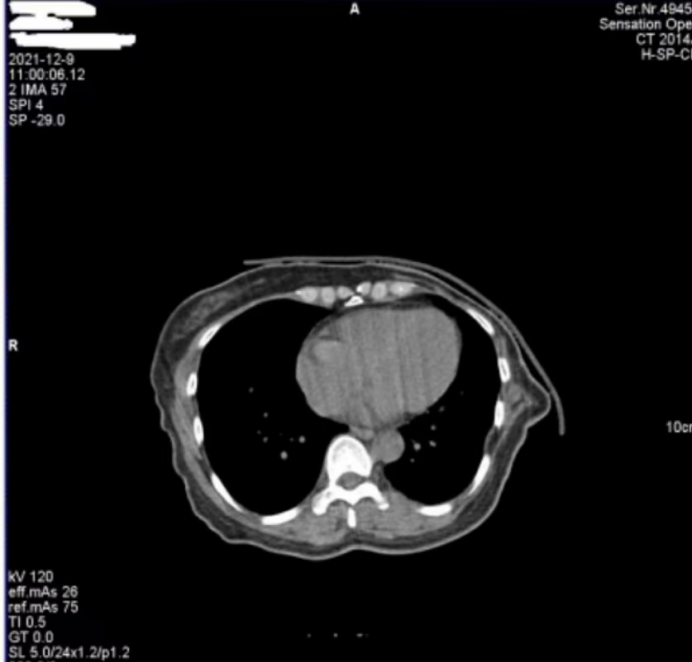

医院反映,西门子Definition型CT机在进行患者扫描时,图像上会偶发两种伪影。一种是斜线状伪影(图 1),另一种是中心不规则高密度伪影(图 2)。其中,斜线状伪影对诊断影响较大,时常导致医生无法准确判断患者病灶情况,医院希望我们尽快排查并解决问题。

图1

对于图 1 中的斜线状伪影,我们第一时间查看了设备的错误日志和球管历史记录,然而并未发现球管存在打火情况的相关信息。但仔细观察图 1 中的 S35C0,结合我们多年的维修经验,这一参数特征明确指向在当时的扫描曝光时刻,球管存在打火现象。球管打火会直接干扰射线的稳定输出,进而在图像上形成这种斜线状伪影,这也解释了为何该伪影会对诊断造成较大影响。